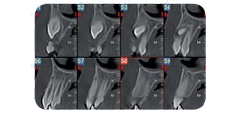

Radiografia specifica per la bocca

Lo studio si avvale di specifiche strumentazioni per assicurarti un’accurata analisi ortodontica. In primis, lo staff medico si affida all’alta tecnologia del sistema Cone Beam NewTon 5G XLUno, fondamentale per settori medici quali implantologia, endodonzia, chirurgia orale e ortodonzia, in grado di creare immagini 3D capaci di mostrare patologie potenziali e anomalie strutturali con una precisione senza precedenti; dall’altra si sottolinea la presenza della tecnologia SafeBeam™, il sistema più sicuro sia per i pazienti che per lo staff medico. Grazie a questo strumento, gli esperti eliminano qualsiasi possibilità di esposizioni radioattive, mantenendo un contrasto dell’immagine nitido e definito, a prescindere dalle dimensioni anatomiche o dalla densità ossea osservata.